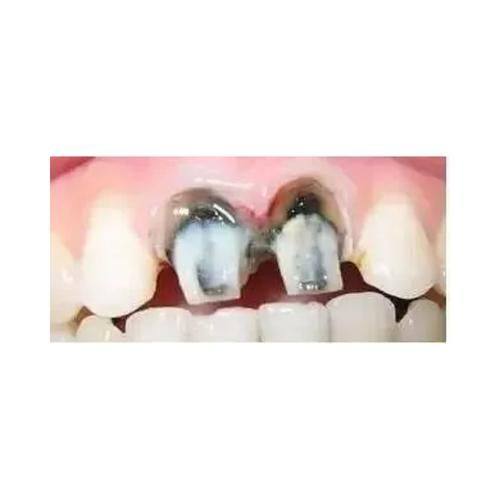

根管治疗:借助精良的数字化设备精细定位病灶,由专精医生操作,能有效清除根管内感染物质,缓解牙齿疼痛,保留患牙,治疗过程注重患者舒适体验。